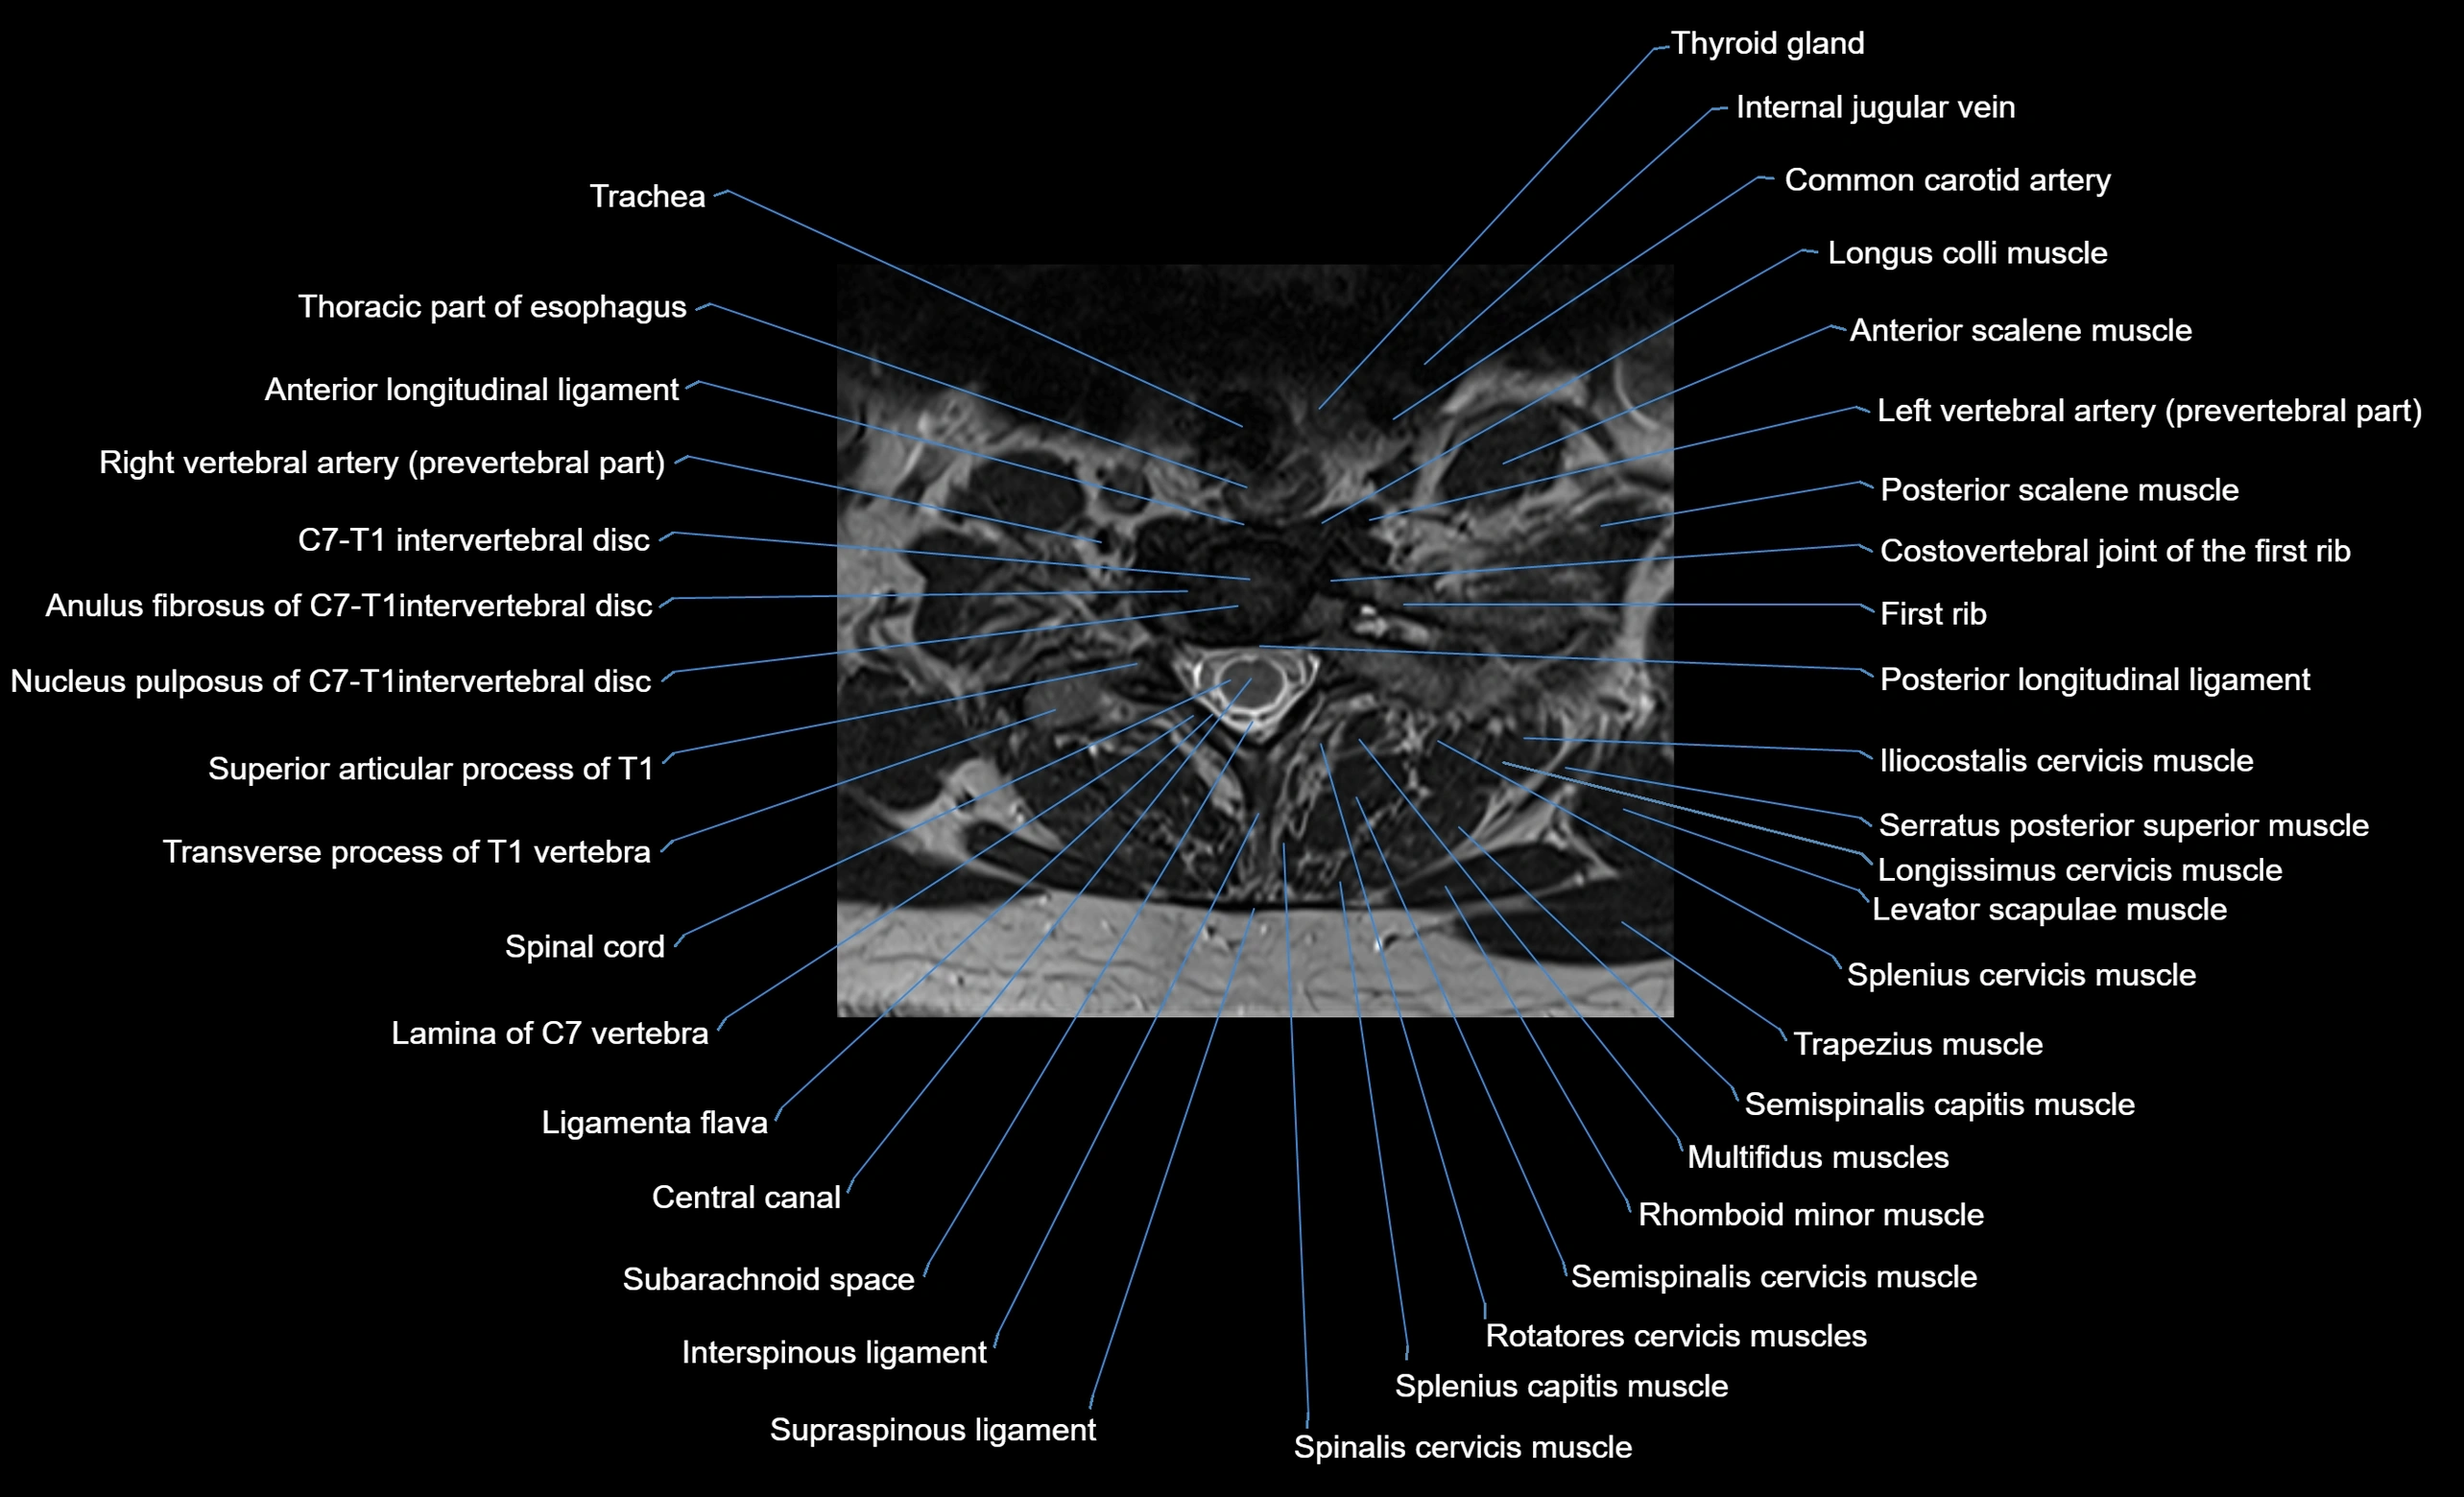

MRI appearance

T1-weighted images:

• Annular epiphysis: Low signal cortical rim at the vertebral margin

• Adjacent marrow: Intermediate-to-high signal in the vertebral body

• Disc interface: Clear delineation between bone and annulus

T2-weighted images:

• Annular epiphysis: Low signal intensity line

• Endplate cartilage (in younger patients): Intermediate signal

• Intervertebral disc: High signal nucleus pulposus

STIR:

• Annular epiphysis: Low signal cortical rim

• Adjacent marrow: Suppressed fat signal with preserved bony outline

• Utility: Highlights marrow and endplate interface in developing spine

MRI image

image